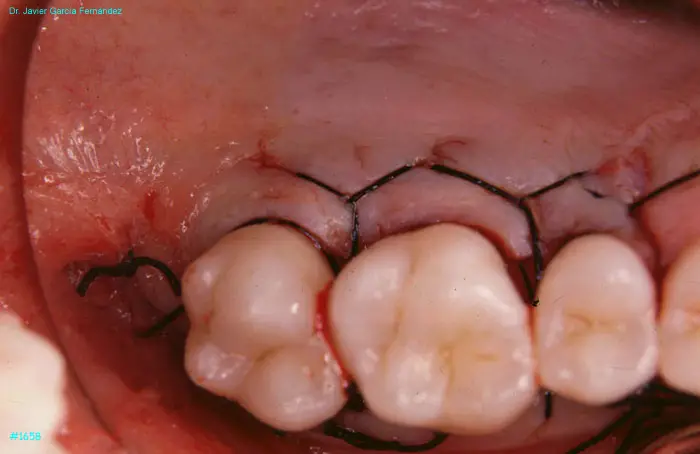

Atlas of Surgical Techniques in Periodontics. Chapter IV. Atlas de Técnicas Quirúrgica en Periodoncia

image 171